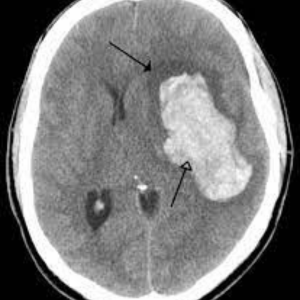

শিশুদের ক্যান্সার